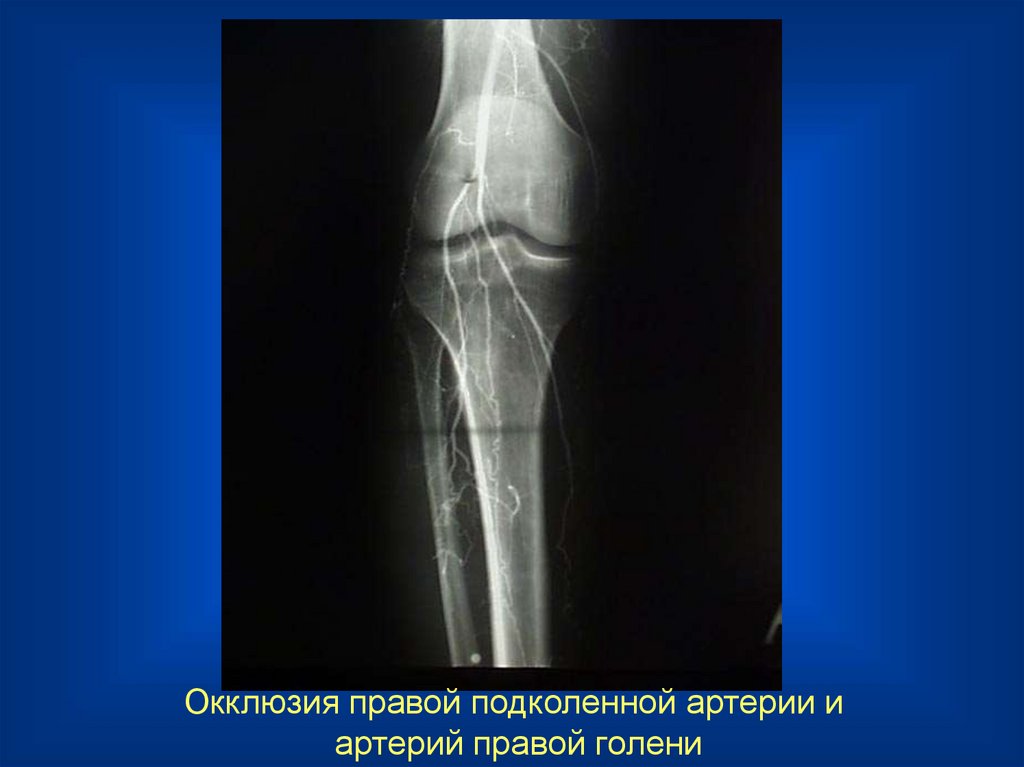

Окклюзия правой подколенной артерии и

артерий правой голени